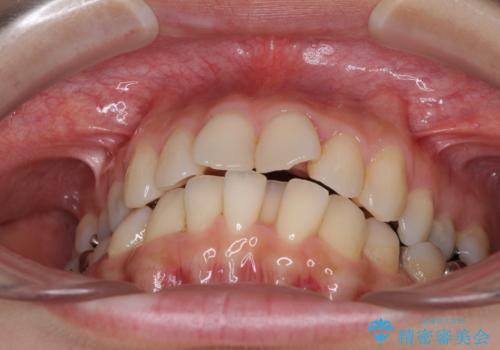

- 上下のデコボコと奥歯の咬みにくさを気にして来院された患者様です。

上顎骨の幅が下顎骨よりも小さいので、拡大装置により骨幅を広げて上下関係を改善し、その後インビザラインにて歯並びを整えることとしました。

上下の骨幅を改善したことで、スムーズに歯列矯正を行うことができました。

矯正治療中に近医で銀歯を外す治療を開始したため、治療後に奥歯の咬み合わせが不十分ですが(こちらは近医での治療により改善するとのこと)、歯列と咬み合わせが改善され、患者様には大変満足していただきました。